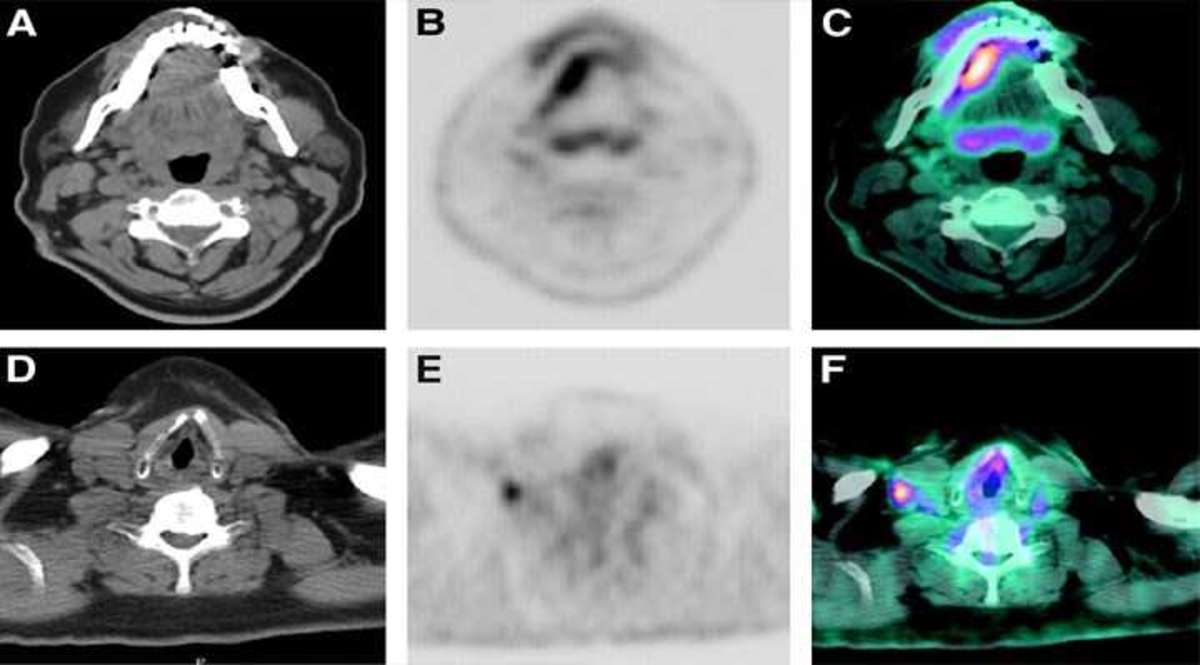

» Extension of the lesion and the spread of cancerous cells are precisely determined through the PET scan. Cancer cells have a tendency to grow rapidly and attack other associated organs. It has to be promptly determined in order to find the hotspots and treat the target specific locations accurately.